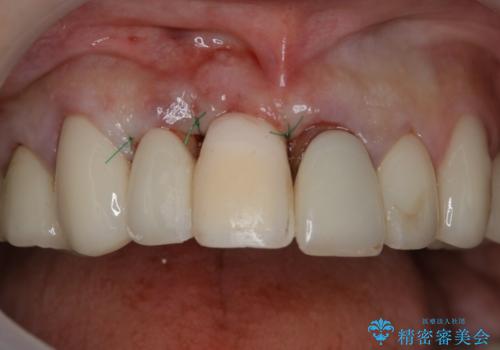

- 事故による外傷で前歯に歯根が真っ二つに折れてしまい、保存不可能となってしまった部分にインプラント治療を計画しました。

患者様のご要望もあり、審美性の確保ができる抜歯早期埋入→埋入後即時荷重という手術法を取りました。

近年、インプラントの素材や手術法の研究が進み、保存不可能となった歯牙に対して抜歯してすぐインプラントを埋入し、さらに直後から仮歯がを入れ噛むことができる【抜歯即時埋入】【即時荷重】という技法が確立されました。

従来、前歯部分のインプラントでは周囲に残っている自身の歯に仮歯を張り付けることで審美性を保ってきましたが、脱離を繰り返したり食事に耐える強度を保つのが難しいという側面がありました。

それと比較すると、今回の方法では骨にしっかりと固定されているインプラントに単独で仮歯を装着することができるためフロスも通せますし、ある程度負荷のかかる食事も気にせずできるようになります。